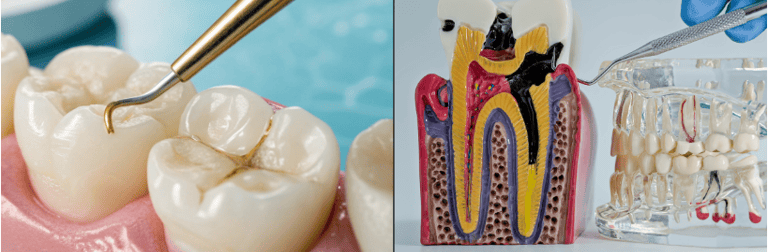

Restaurações;

Tratamento de Canal;

Pinos Intra-radiculares;